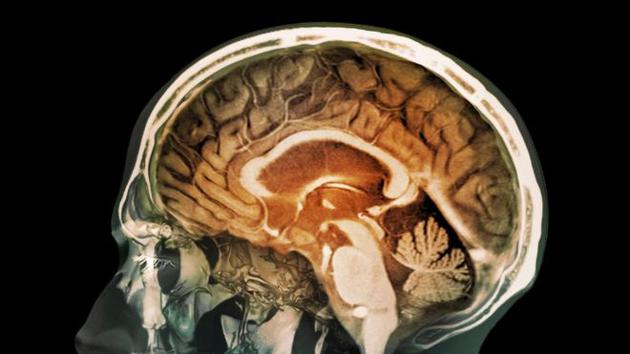

污染空氣毒性微??芍苯舆M人類大腦 或誘發(fā)老年癡呆

最新研究顯示,人體大腦組織中存在微小的磁鐵微粒,這些微??赡苁强諝馕廴舅?。研究分析表明,大腦中存在大量磁鐵微粒,可能誘發(fā)阿爾茨海默癥和其他神經(jīng)退行性疾病。

新浪科技訊 北京時間11月29日消息,據(jù)國外媒體報道,空氣污染中的磁鐵微粒被懷疑具有毒性,吸入人體可直接進入大腦,可能誘發(fā)老年癡呆癥等疾病。

目前這項最新研究首次證實具有污染性的磁鐵微粒能夠進入人類大腦,2016年初,世界衛(wèi)生組織警告稱,空氣污染每年導(dǎo)致300多萬人過早死亡。